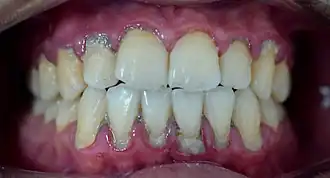

Calculus formation is associated with a number of clinical manifestations, including bad breath, receding gums and chronically inflamed gingiva. Brushing and flossing can remove plaque from which calculus forms; however, once formed, calculus is too hard (firmly attached) to be removed with a toothbrush. Calculus buildup can be removed with ultrasonic tools or dental hand instruments (such as a periodontal scaler).

Plaque accumulation causes the gingiva to become irritated and inflamed, and this is referred to as gingivitis. When the gingiva become so irritated that there is a loss of the connective tissue fibers that attach the gums to the teeth and bone that surrounds the tooth, this is known as periodontitis. Dental plaque is not the sole cause of periodontitis; however it is many times referred to as a primary aetiology. Plaque that remains in the oral cavity long enough will eventually calcify and become calculus.[18] Calculus is detrimental to gingival health because it serves as a trap for increased plaque formation and retention; thus, calculus, along with other factors that cause a localized build-up of plaque, is referred to as a secondary aetiology of periodontitis.

When plaque is supragingival, the bacterial content contains a great proportion of aerobic bacteria and yeast,[20] or those bacteria which utilize and can survive in an environment containing oxygen. Subgingival plaque contains a higher proportion of anaerobic bacteria, or those bacteria which cannot exist in an environment containing oxygen. Several anaerobic plaque bacteria, such as Porphyromonas gingivalis,[21] secrete antigenic proteins that trigger a strong inflammatory response in the periodontium, the specialized tissues that surround and support the teeth. Prolonged inflammation of the periodontium leads to bone loss and weakening of the gingival fibers that attach the teeth to the gums, two major hallmarks of periodontitis. Supragingival calculus formation is nearly ubiquitous in humans,[22][23][24] but to differing degrees. Almost all individuals with periodontitis exhibit considerable subgingival calculus deposits.[18] Dental plaque bacteria have been linked to cardiovascular disease[25] and mothers giving birth to pre-term low weight infants,[26] but there is no conclusive evidence yet that periodontitis is a significant risk factor for either of these two conditions.[27]